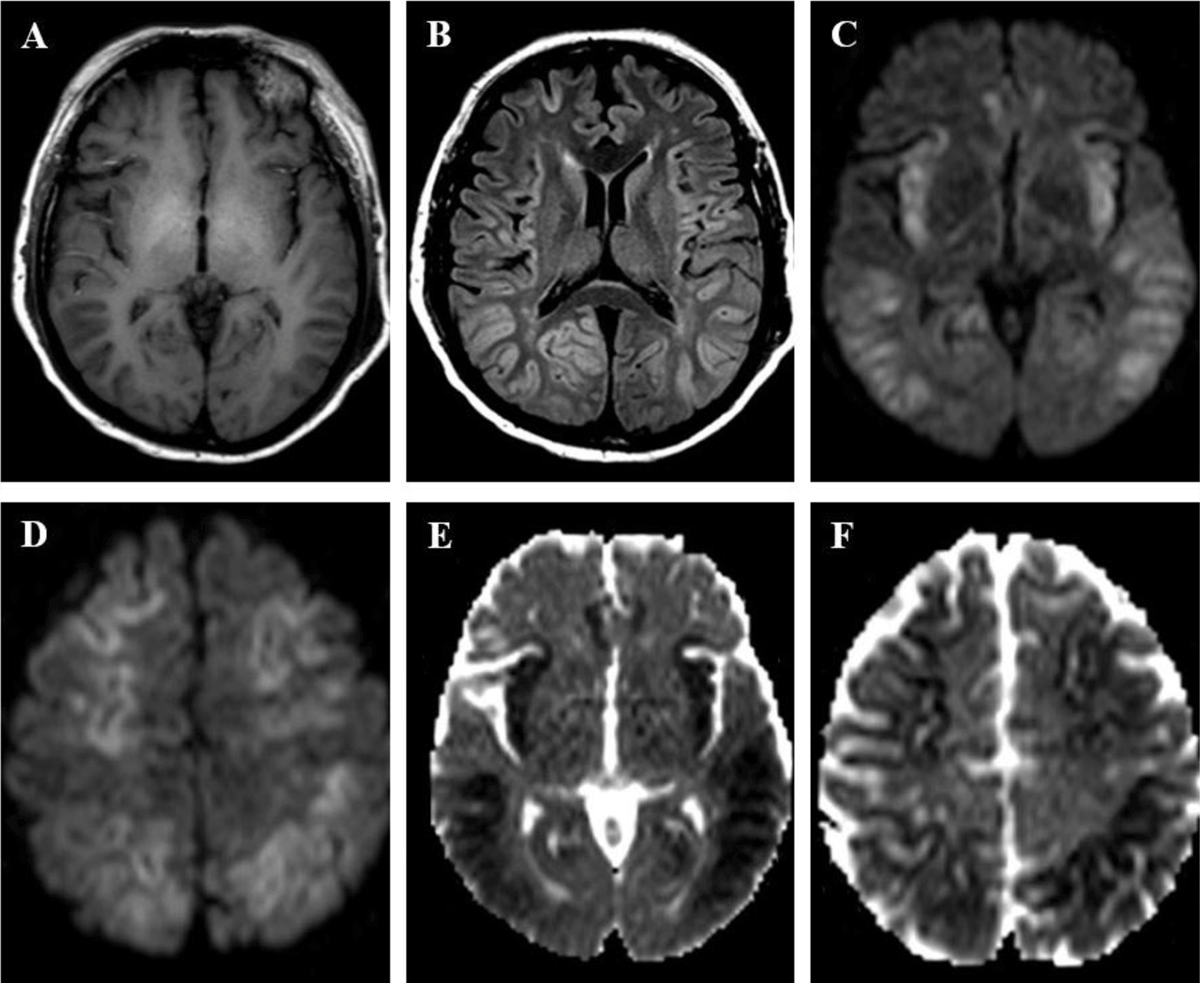

Figure 3

A 49-year old man was found in a coma. Clinical and laboratory findings indicated decompensated cirrhosis with encephalopathy. (A) T1-weighted imaging shows high signal in globi pallidi, suggesting underlying chronic hepatic disease. (B) FLAIR image shows bilateral and symmetric signal abnormalities in insular, cingulate, frontal and parietal cortices. (C, D) DWI (b-value = 1000 s/mm2) and (E, F) ADC show respectively high and low signal in affected cortices, consistent with cytotoxic edema, with sparing of occipital and peri-rolandic cortices.